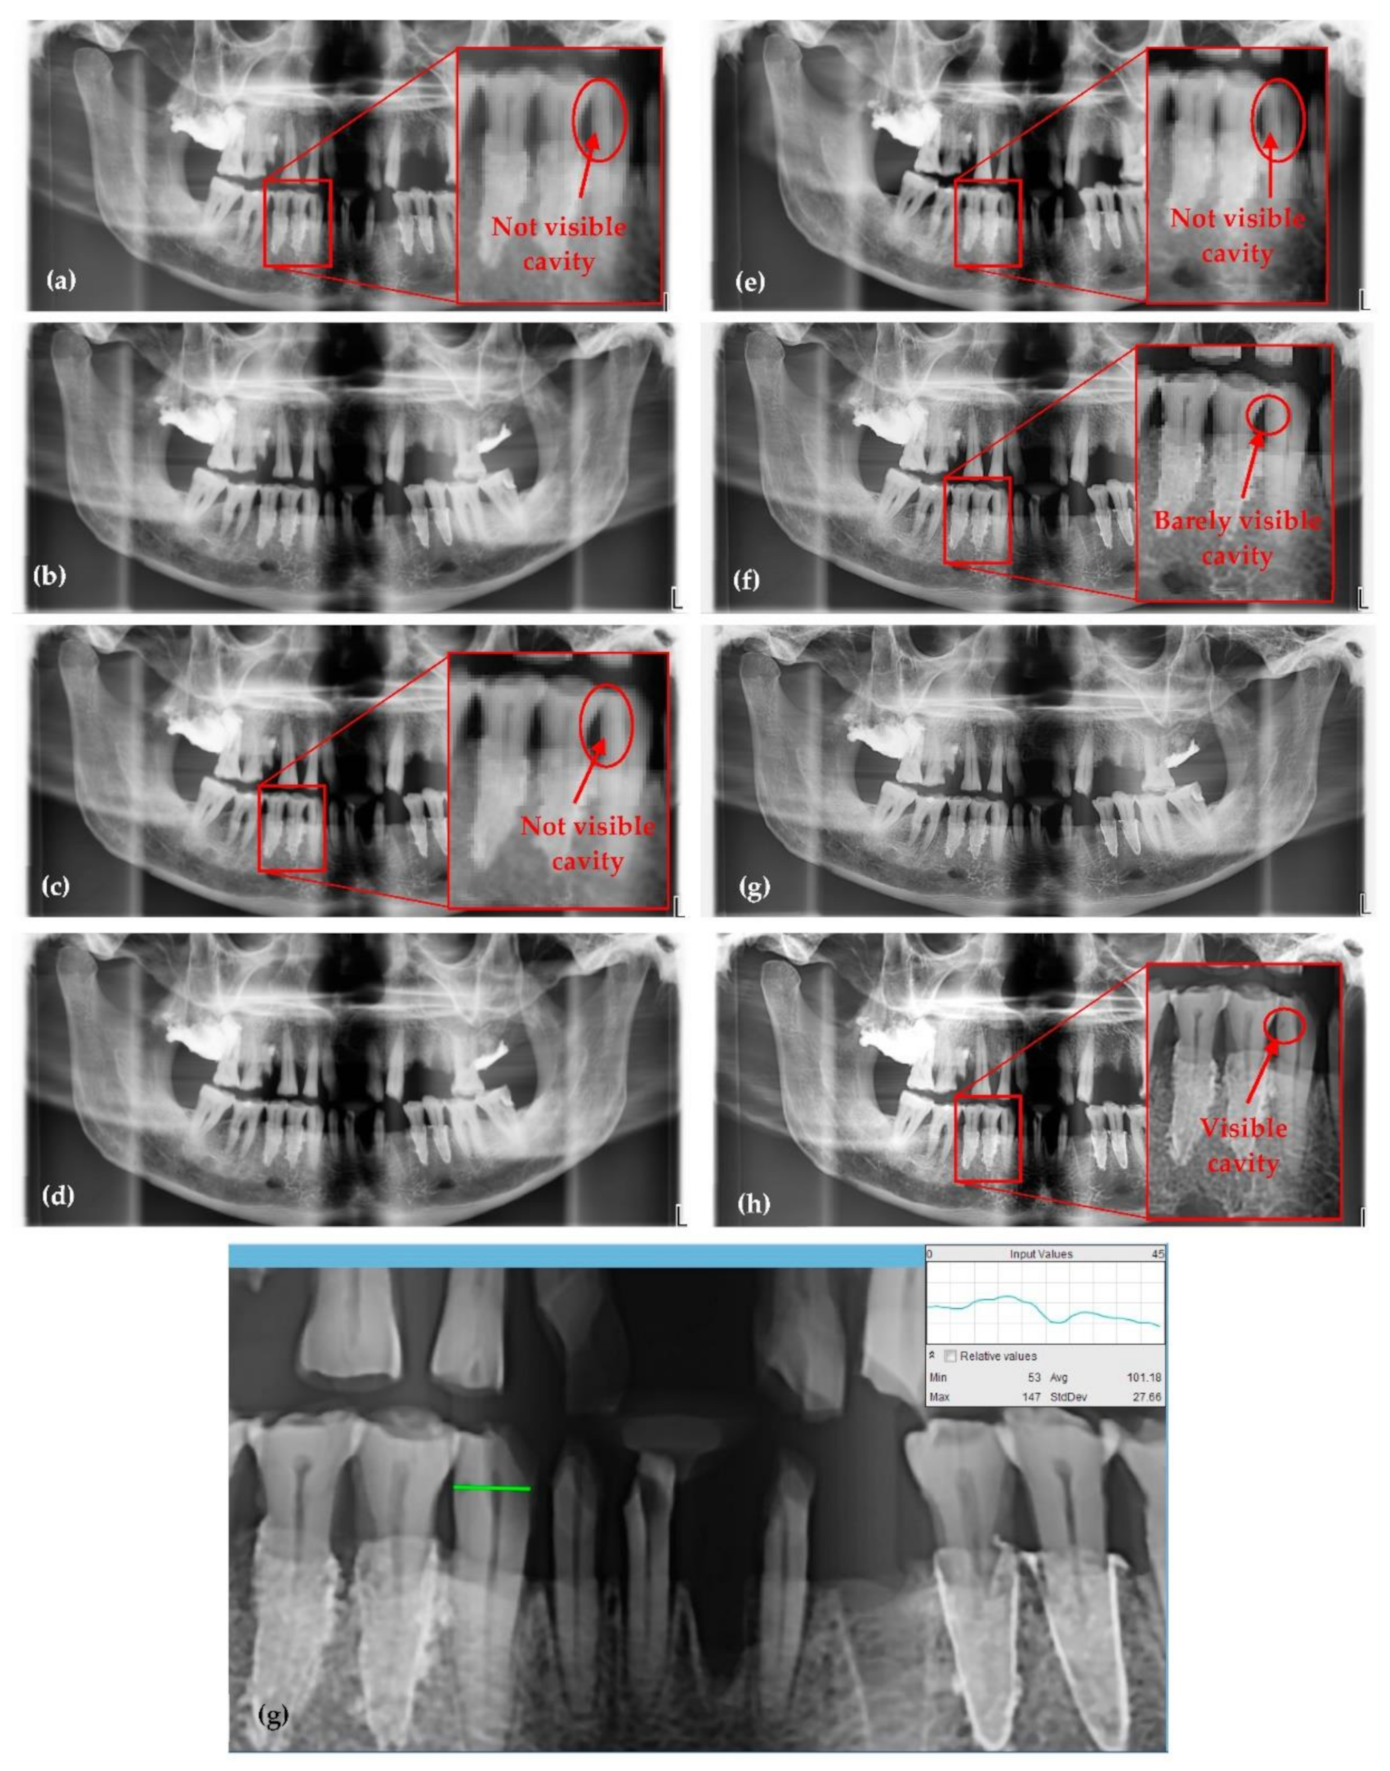

3.1. Optimized Protocol with OCT for X-ray Imaging Calibration. Panoramic Radiography

| Panoramic Radiographs (Figure 8) | Anode Voltage (kV) | Current Intensity (mA) | Exposure Time (s) | Radiation Dose (µSv) | ||

|---|---|---|---|---|---|---|

| a | 60 | 1 | 13.7 | 0.65 | 0.2 | 4.15 |

| b | 61 | 2 | 15 | 1.74 | 0.34 | 4.1 |

| c | 62 | 3.2 | 15 | 2.89 | 0.3 | 4 |

| d | 64 | 4 | 15 | 3.88 | 0.19 | 3.92 |

| e | 66 | 6.3 | 15 | 6.54 | 0.43 | 3.67 |

| f | 68 | 8 | 15 | 8.84 | 0.36 | 3.57 |

| g | 70 | 10 | 15 | 11.68 | 0.46 | 3.45 |

| h | 72 | 11 | 15 | 13.72 | 0.58 | 3.35 |

|

Panoramic Radiographs (Figure 8) | ||||||

| a | 3 | 3479 | 2104.47 | 1122.57 | 0.998 | 3.096 |

| b | 17 | 3377 | 2031.94 | 1094.54 | 0.989 | 3.069 |

| c | 20 | 3485 | 2012.62 | 1102.82 | 0.988 | 3.141 |

| d | 32 | 3317 | 1975.26 | 1060.52 | 0.980 | 3.097 |

| e | 31 | 3489 | 2106.08 | 1078.73 | 0.982 | 3.205 |

| f | 22 | 3456 | 2081.59 | 1056.53 | 0.987 | 3.250 |

| g | 70 | 3576 | 2172.58 | 1083.91 | 0.961 | 3.234 |

| h | 18 | 3593 | 2117.34 | 1095.44 | 0.990 | 3.263 |